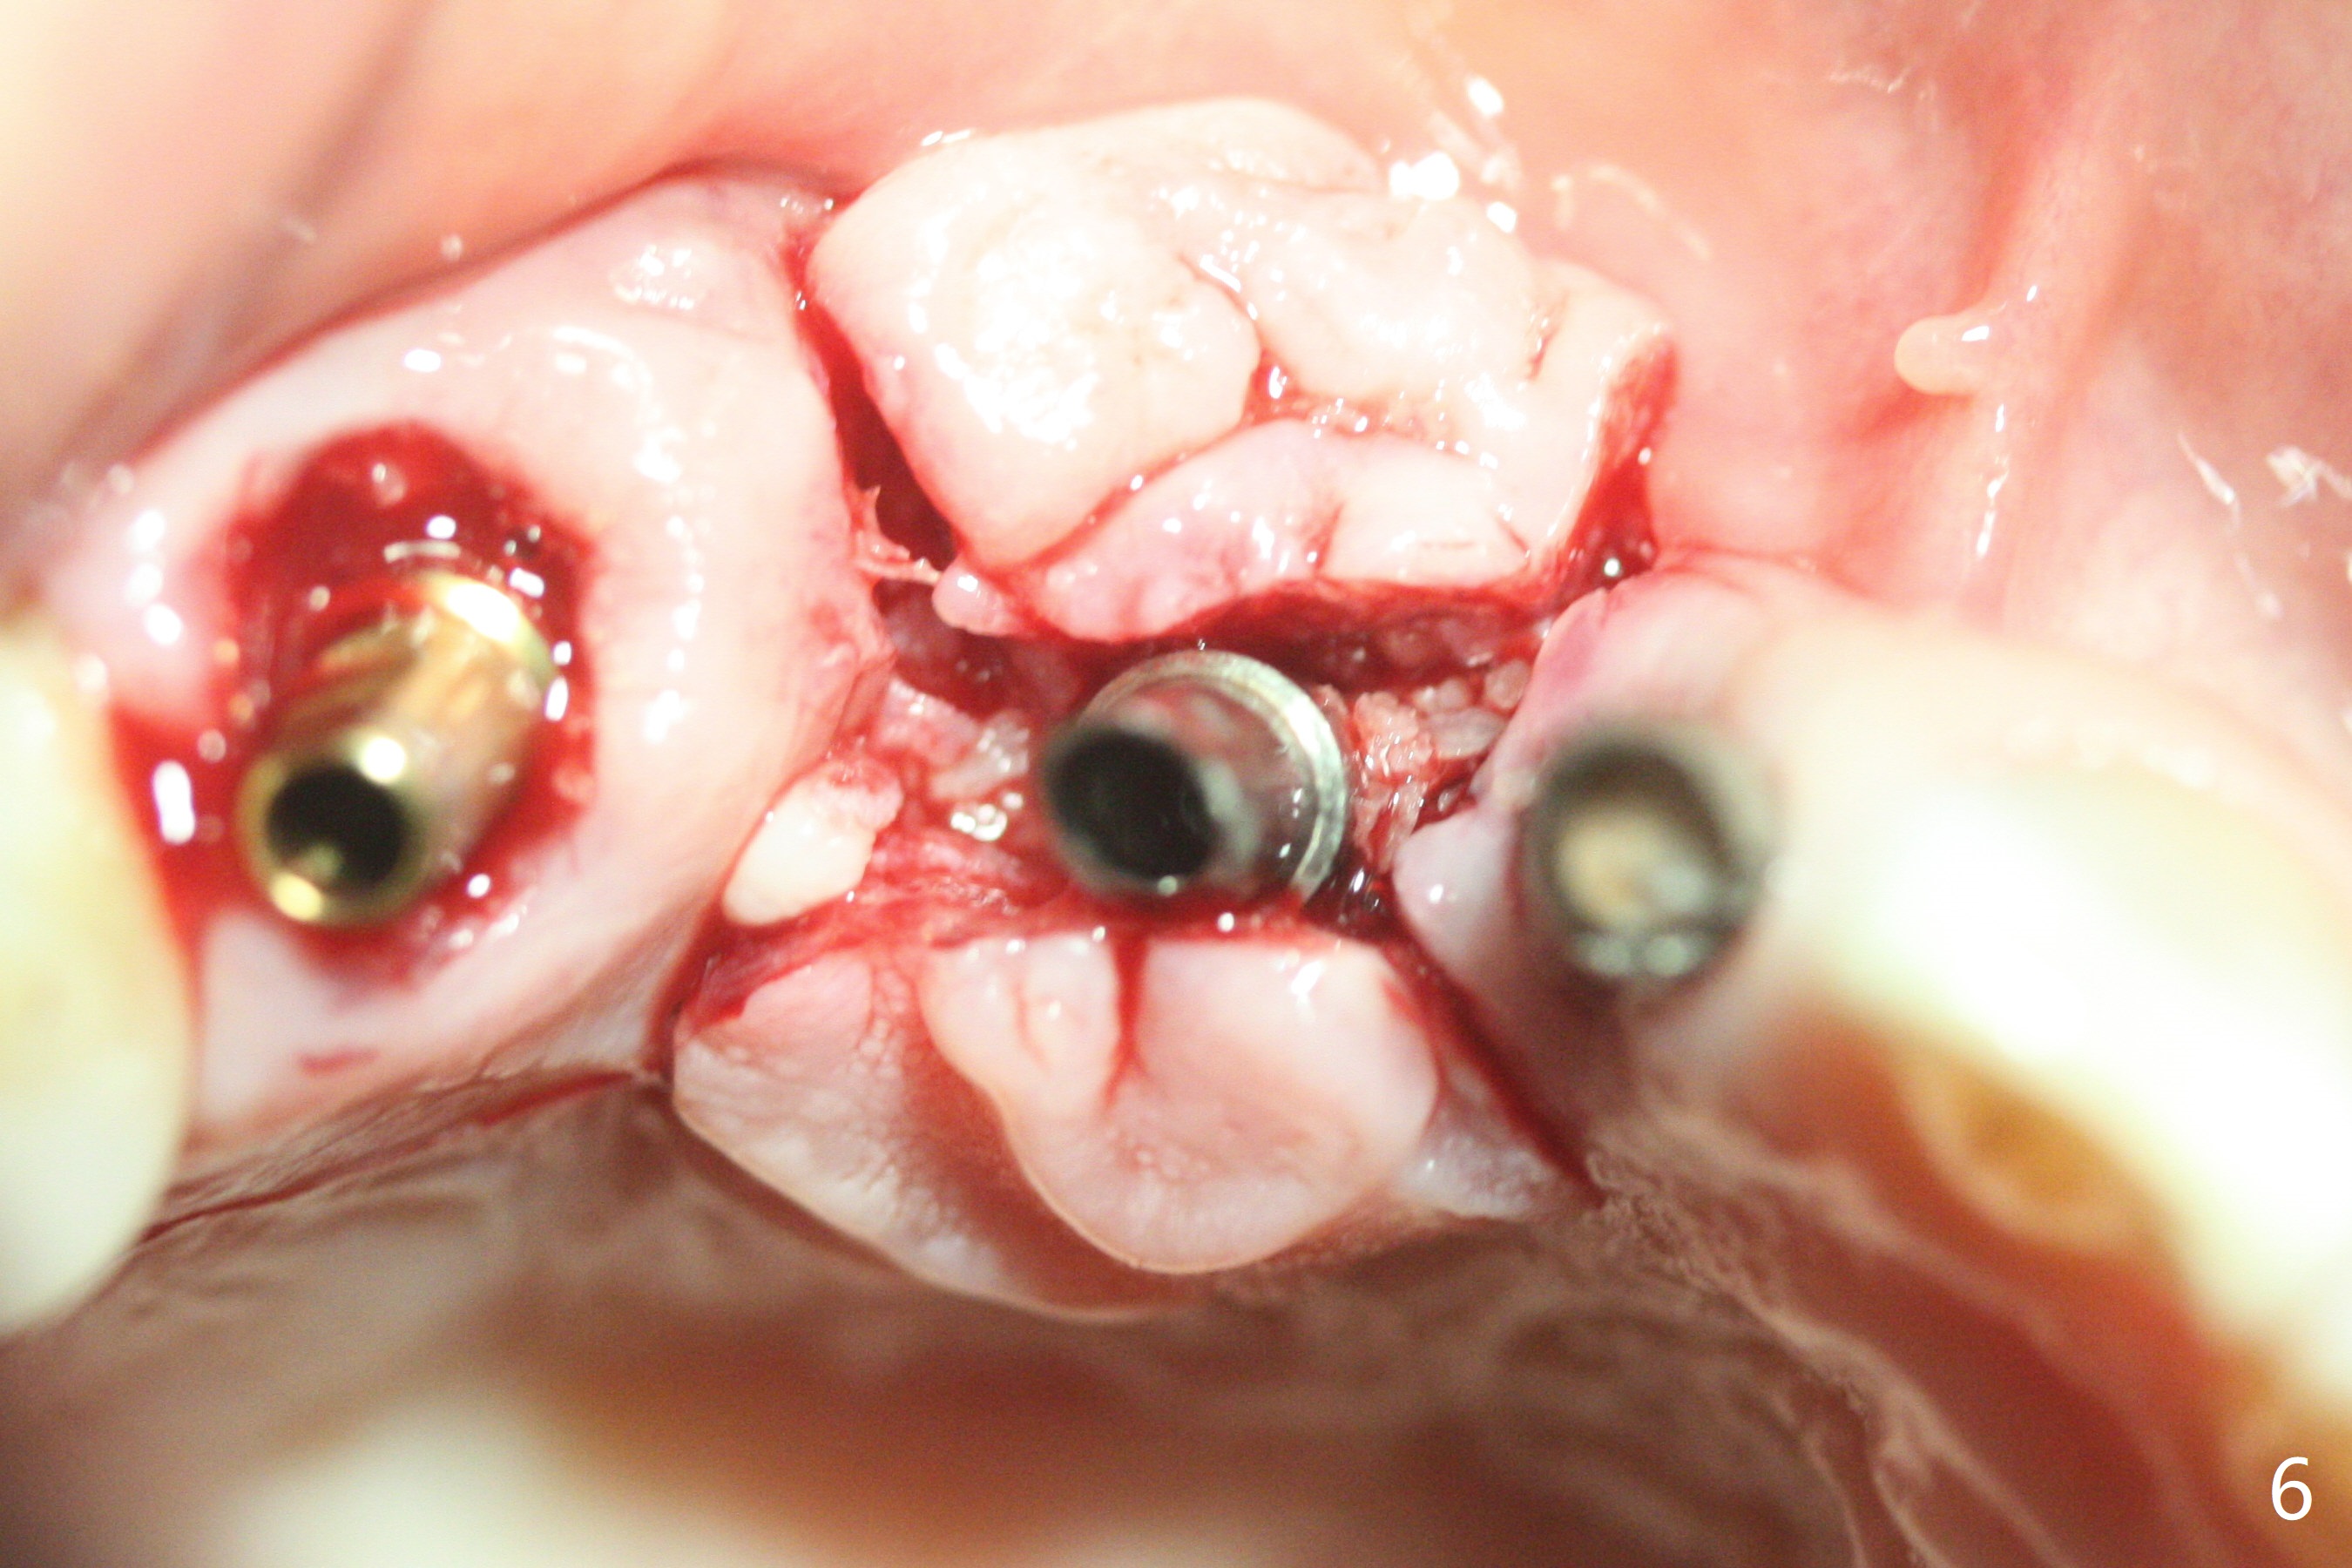

在6,7号牙位牙槽嵴切口,翻瓣,找不到上次放置的tenting screw,不过7号牙位骨质虽然低,够宽的,开始钻洞(图四),植入3.8乘8.5毫米植体,扭力足够(图五),近中舌侧暴露螺纹堆加骨粉(图五*),然后放置基台,再次在后者周围放置骨粉(图五至七),覆盖两张PRF膜后缝合(图八),最后在三个箭头周围放置牙周敷料。术后CT显示植体与tenting screws(图九,十箭头)有一定距离,但是5号牙植体颊侧根尖穿孔(图九 *)。如果植体不脱落,需做侧方切口植骨。术后七天7号植体腭侧肿胀(图十一 *),切开没有脓水,插入牙胶尖,它末端指向7号植体周围tenting screw。后者可能需要拔除,同时5号牙颊侧根尖植骨,但是为时太早,可能打搅骨粉生长。术后两周腭侧肿胀没有消失,但是不痛,继续观察。术后接近6个月,软组织正常(图十三),但是5,7植体周围没有骨质(图十四,五)。由于近中tenting screws周围软组织触痛(局麻不全情况下),螺钉取出(图十六,七(*)),而远中螺钉好像有帮助5植体螺纹骨粉撑起,所以留下(腭侧穿孔部分去除),最后放置粘性骨粉(图十八:*)和PRF膜(两张由7基台打孔固定)。